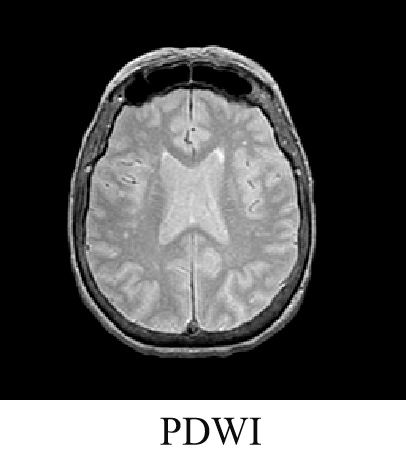

磁共振成像(Magnetic Resonance Imaging , MRI)是利用原子核在强磁场内发生核磁共振产生的信号经图像重建的成像技术。

磁共振成像过程中,射频脉冲激发后所记录到的信号强度的大小主要与以下因素有关:

一是生物组织本身的因素,包括T1、T2和质子密度等;

二是脉冲序列的形式。

T2加权:

PD加权: